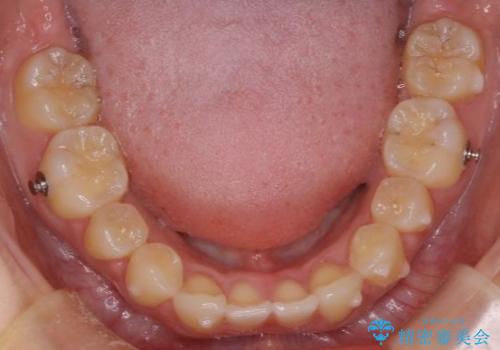

- 患者様は、上下の噛み合わせのバランスが悪く、特に上顎の前歯の突出を気にされて来院されました。診査の結果、下顎の歯並びに合わせて上顎を後方へ移動させる必要があると判断し、上顎の小臼歯2本を抜歯することを提案しました。目立たない矯正を希望されたため、**インビザライン(マウスピース矯正)**を選択。計画的にスペースを作りながら、バランスの取れた歯並びを目指しました。

治療はまず、上顎の小臼歯を2本抜歯し、そのスペースを利用して前歯を後方へ移動させました。インビザラインはアタッチメントを併用し、より効率的に歯を動かせるよう調整。定期的なチェックとアライナーの交換を続け、約3年かけて理想的な歯並びと噛み合わせを実現しました。治療後はリテーナーを使用し、安定した状態を維持。患者様からは「口元がスッキリし、横顔の印象も変わった」と嬉しいお声をいただきました。